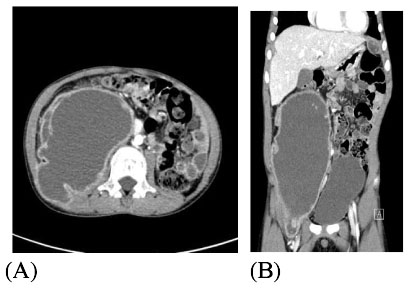

(A). A cross sectional view of the abdominal CT with contrast shows huge iliopsoas abscess (27 × 7.6 × 9.5 cm) with well enhancing rim on the right side of the abdomen. (B). In an axial view, variable sized multiple intraabdominal abscesses were also seen under the subcapsular area of the liver and left subphrenic area.

Fig. 1 (A). A cross sectional view of the abdominal CT with contrast shows huge iliopsoas abscess (27 × 7.6 × 9.5 cm) with well enhancing rim on the right side of the abdomen. (B). In an axial view, variable sized multiple intraabdominal abscesses were also seen under the subcapsular area of the liver and left subphrenic area.